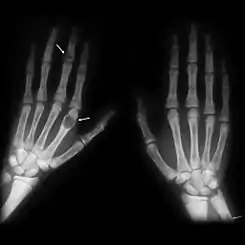

Tumores pardos en las manos de un paciente con hiperparatiroidismo.

Los tumores pardos son tumores del hueso que se producen como consecuencia de un exceso de actividad osteoclástica, como ocurre en el caso del hiperparatiroidismo. Consiste en tejido fibroso, hueso no laminar (hueso embrionario) y la vascularizción de soporte, pero no hay en ellos matriz ósea. En las radiografías se ven radiolucentes, apareciendo como lesiones líticas.

Su característica coloración marrón se debe a la deposición de hemosiderina en las lesiones quísticas osteolíticas.